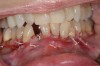

Fig 9. SFOT intraoperative surgical photograph; note the correlation of the CBCT scan in Fig 7 with the surgical findings, confirming the lack of blood supply even after completion of corticotomies.

Figure 9